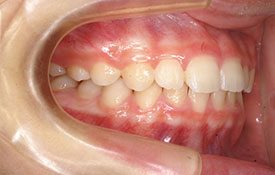

インビザラインの治療例:CASE-1

| プロフィール | 42歳 女性 |

| 所見 | 他院で行われた矯正歯科治療後の後戻りに悩まれて来院されました。 アイライナーの装着は、1日平均20時間ほどでした。 |